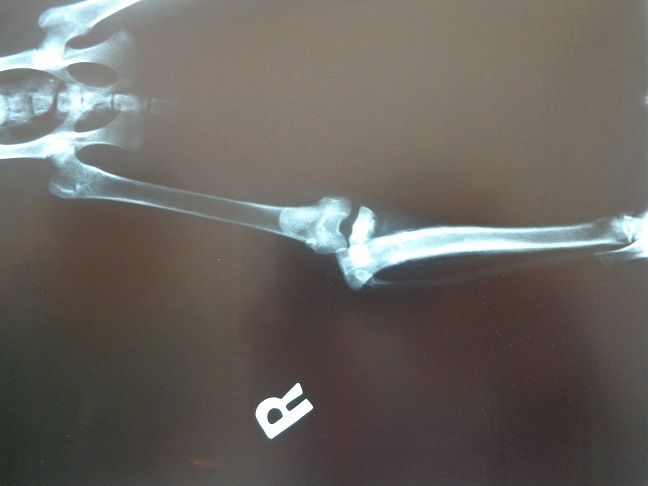

主題: 右側腿勁骨生長板斷裂的小喵 申請者姓名: Shannon Chen 花色: 申請日期: 2014-10-15 22:50:54 申請者部落格: 申請者臉書網址: 所在縣市/合作醫院: 新北市/成蹊動物醫院 治療費用: 10000元 需求人數: 12人 已結案 (2015-02-24 12:21:31) 報名人員: 黃美美(已付款)、黃美美、WeiLin Chen x2(已付款)、徐荷詠(已付款)、Sweettpg(已付款)、Jimmy Li(已付款)、小娃(已付款)、Mei Mei Liao(已付款)、Coffeemilk(已付款)、chiawei x2(已付款)、fnnny(已付款)、 候補人員: 動物病情說明: 咪醬是一隻3~4個月的小喵,於9月中旬出現在我平日餵養的區域(新店土地公廟旁),當時牠體型太小還不能做TNR,想餵大了一些再做,後來餦食了4天後突然消失,12天後突然出現,無外傷但發現牠走路一跛一跛,看到牠的右後腿斷掉往後縮,趕緊用誘籠抓喵送醫.

醫生檢查拍了X光片說牠的右側勁骨生長板斷裂骨折必須做手術.

10/8做手術,共釘了三根鋼釘固定,二個星期後回診拆線